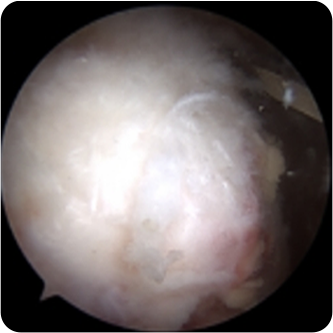

회전근개파열의 여러 모습들

회전근개파열의